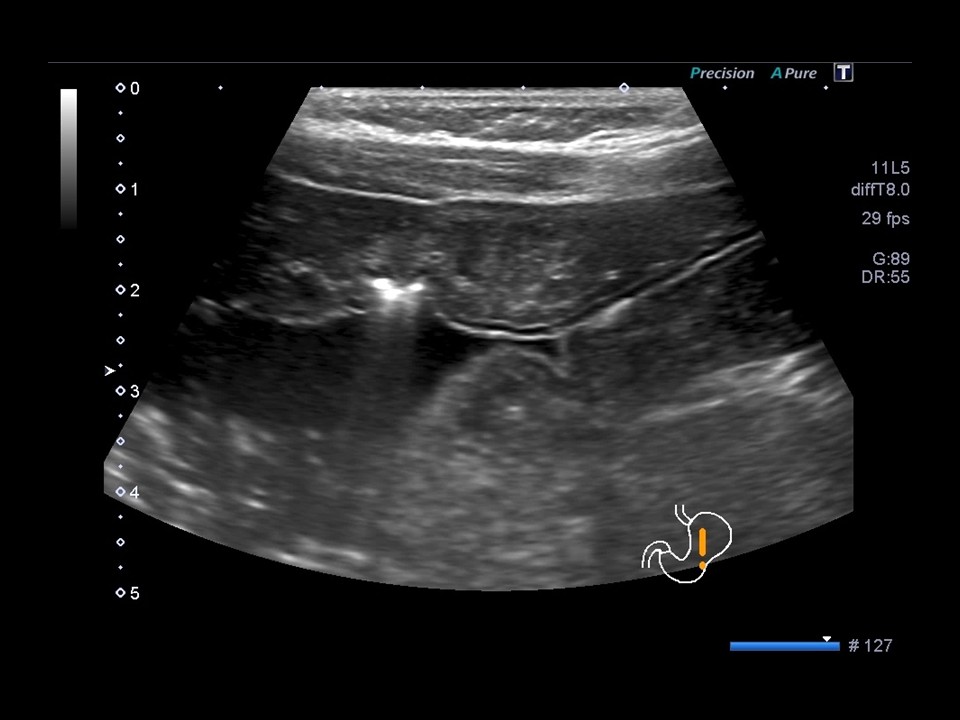

最優秀賞

岩田 好隆

東京女子医科大学付属足立医療センター

診断名急性胃粘膜性病変および胃潰瘍疑い

患者:10歳代 男性

使用機種:Canon Aplio 400

周波数:8.0 MHz

胃体部から幽門部にかけ全周性の著明壁肥厚(第3層中心)と前壁には高輝度エコーを認め、急性胃粘膜性病変と潰瘍形成を疑いました。

(エコー後施行の胃内視鏡と病理でも同様の結果で、壁肥厚と潰瘍の存在部位がほぼ正解できたことがうれしかったです。)